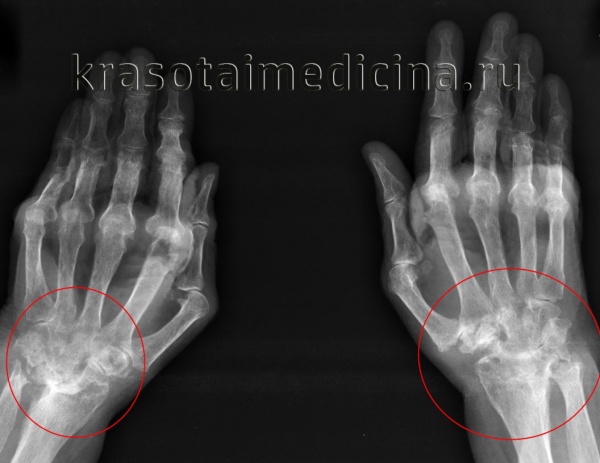

- Рентгенографии. К рентгенологическим критериям ревматоидного артрита относится обнаружение диффузного или пятнистого эпифизарного остеопороза, сужения суставных щелей, краевых эрозий. По показаниям назначается МРТ сустава.

Рентгенография кистей. Поражения суставов при ревматоидном артрите (IV стадия по Штейнброкеру). Костный анкилоз; множественные эрозии суставных поверхностей; подвывих в суставах; остеопороз.